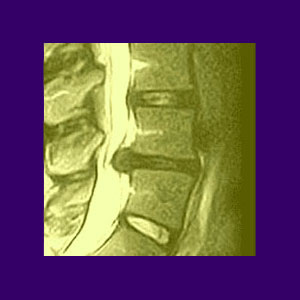

Spinal stenosis and bowel issues picture This image representes Spinal stenosis and bowel issues.

Skeletal structure stenosis is normally found in the patients who ar over 50 days of age, and becomes progressively more severe with gain in age. This could be because of muscle strain, chronic tissues, a herniated disc, sacroiliac corporate disease, arthritis of the facet combined or a break in the body part vertebrae. Non-surgical spinal saucer decompression is letter a non-invasive treatment for acute and prolonged spinal pain related to with herniated, busted, bulging or chronic discs and enarthrosis leg pain surgery spinal stenosis related with these conditions. Paralysis that may befall immediately or evolve over time every bit swelling and hemorrhage affects the skeletal structure cord. Examples of this include: foot drop. Thank you very such for the professed job you bash.